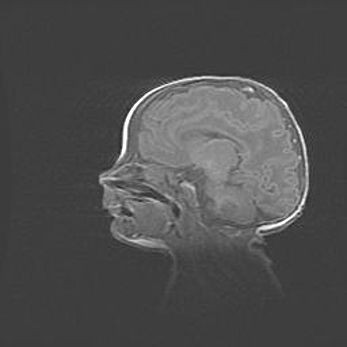

Открытая гидроцефалия.

Возраст: 9 месяцев 12 дней

Вес: 6800 г

Пол: мужской

Окружность головы: 41,5 см

Срок гестации: 28 недель

Гидроцефалия головного мозга у новорожденных имеет характерный признак: опережающий рост окружности головы приводит к визуально хорошо определяемой гидроцефальной форме сильно увеличенного в объёме черепа. Детские неврологи определяют следующие симптомы гидроцефалии у грудничков: выбухающий напряжённый родничок, частое запрокидывание головы, смещение глазных яблок к низу.